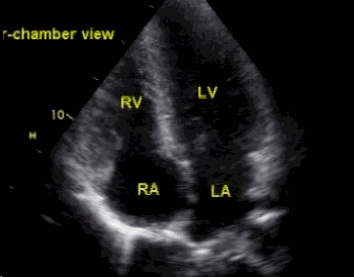

使用双切面(二腔室+四腔室)超声心动图数据训练Mamba模型诊断早期心梗的需求,设计了一个创新性的双路径时空融合Mamba架构(Dual-Path Spatiotemporal Fusion Mamba, DPSF-Mamba)。该架构针对性解决多切面心脏超声的时空特征融合问题,核心思路如下:

独立编码路径:为二腔室(2C)和四腔室(4C)切面分别设计专用Mamba块,适应不同视角的局部结构特征。

2C路径:聚焦左心室前壁、心尖部运动异常(早期心梗敏感区域)。

4C路径:捕获室间隔、侧壁运动及整体心室协调性(诊断关键指标)。